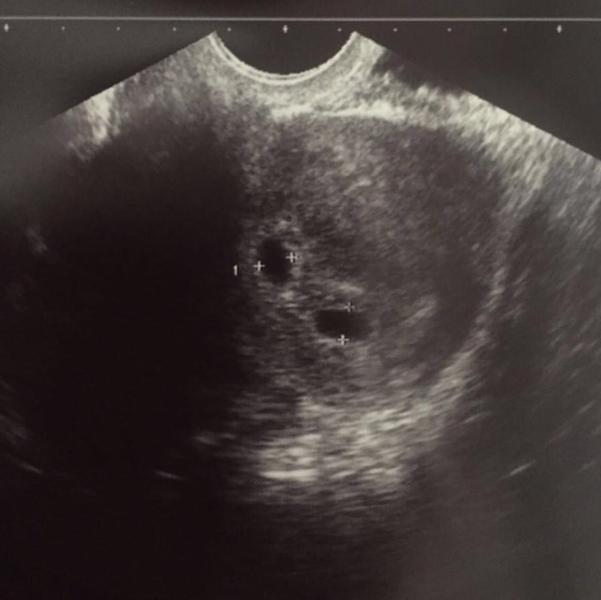

Девочки у меня отличное настроение)) 👻 сегодня сходила с утра на УЗИ показали 2 плода. Я в шоке 😳 час почти плакала)) это так неожиданно для меня 🤗

успокоилась) двойное счастье у меня))